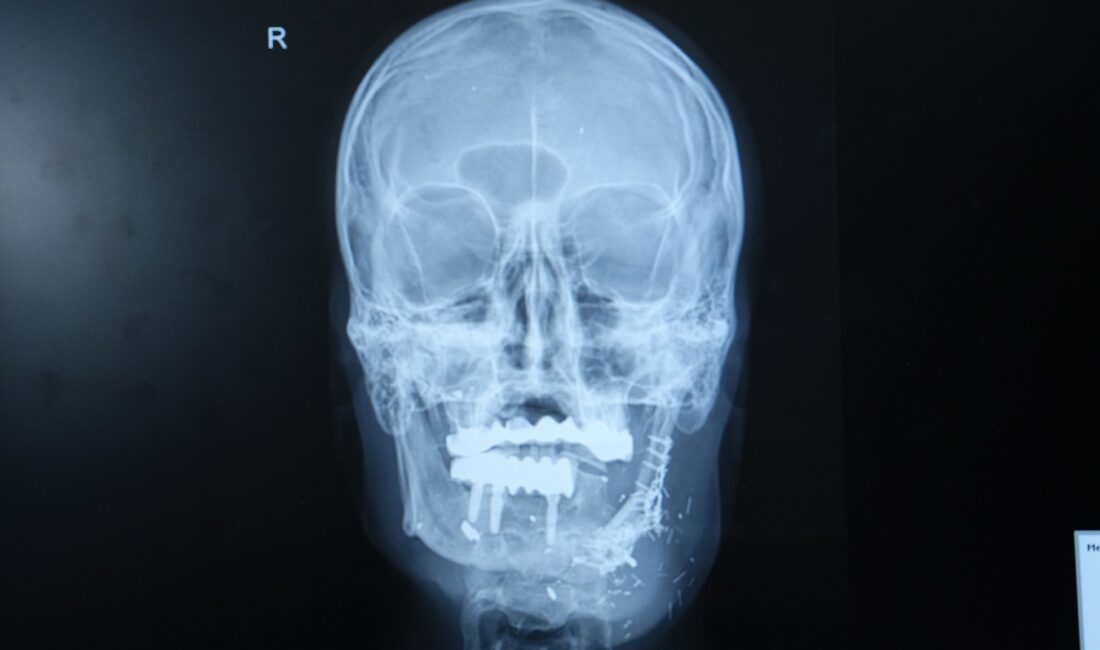

İzzet Baldır, ateşli silah yaralanması nedeniyle çenesinin yarısını kaybetmişti. Daha önce farklı merkezlerde ameliyat olmuş ancak nakiller başarısız olmuştu. Çiğneme ve konuşma gibi temel ihtiyaçlarını karşılamakta zorlanan Baldır, son olarak Doç. Dr. Özkan ile tanıştı. Operasyonda, hastanın bacağından alınan kemik mikrocerrahi yöntemle çeneye nakledildi.

Hastanın durumunun oldukça komplike olduğunu dile getiren Doç. Dr. Burak Özkan, “Hastamız ateşli silah yaralanması sonrası çenesinin yarısını kaybetmişti. Daha önce farklı merkezlerde ameliyat olmuş fakat nakiller başarısız olmuştu. Hem çene bütünlüğünü sağlamak hem de ileride implant yapılabilecek sağlam bir kemik dokusu oluşturmak gerekiyordu. Hastanın bacağından aldığımız kemiği mikrocerrahi yöntemle çeneye naklettik. Damarlara bağlantı yaptık, plaklarla sabitledik. Bu sayede hem fonksiyonel hem de estetik olarak başarılı bir sonuç elde ettik” dedi.

Doç. Dr. Özkan, bu tür vakalarda mikrocerrahinin önemine dikkat çekerek, “Kompozit doku eksikliklerinde vasküler kemik transferi bize büyük avantaj sağlıyor. Hastamız şu an kendi beslenmesini sağlayabiliyor. Önümüzdeki süreçte kemik iyileşmesini tamamladıktan sonra diş implantları yerleştireceğiz ve hastamız çok daha rahat beslenebilecek” ifadelerini kullandı.